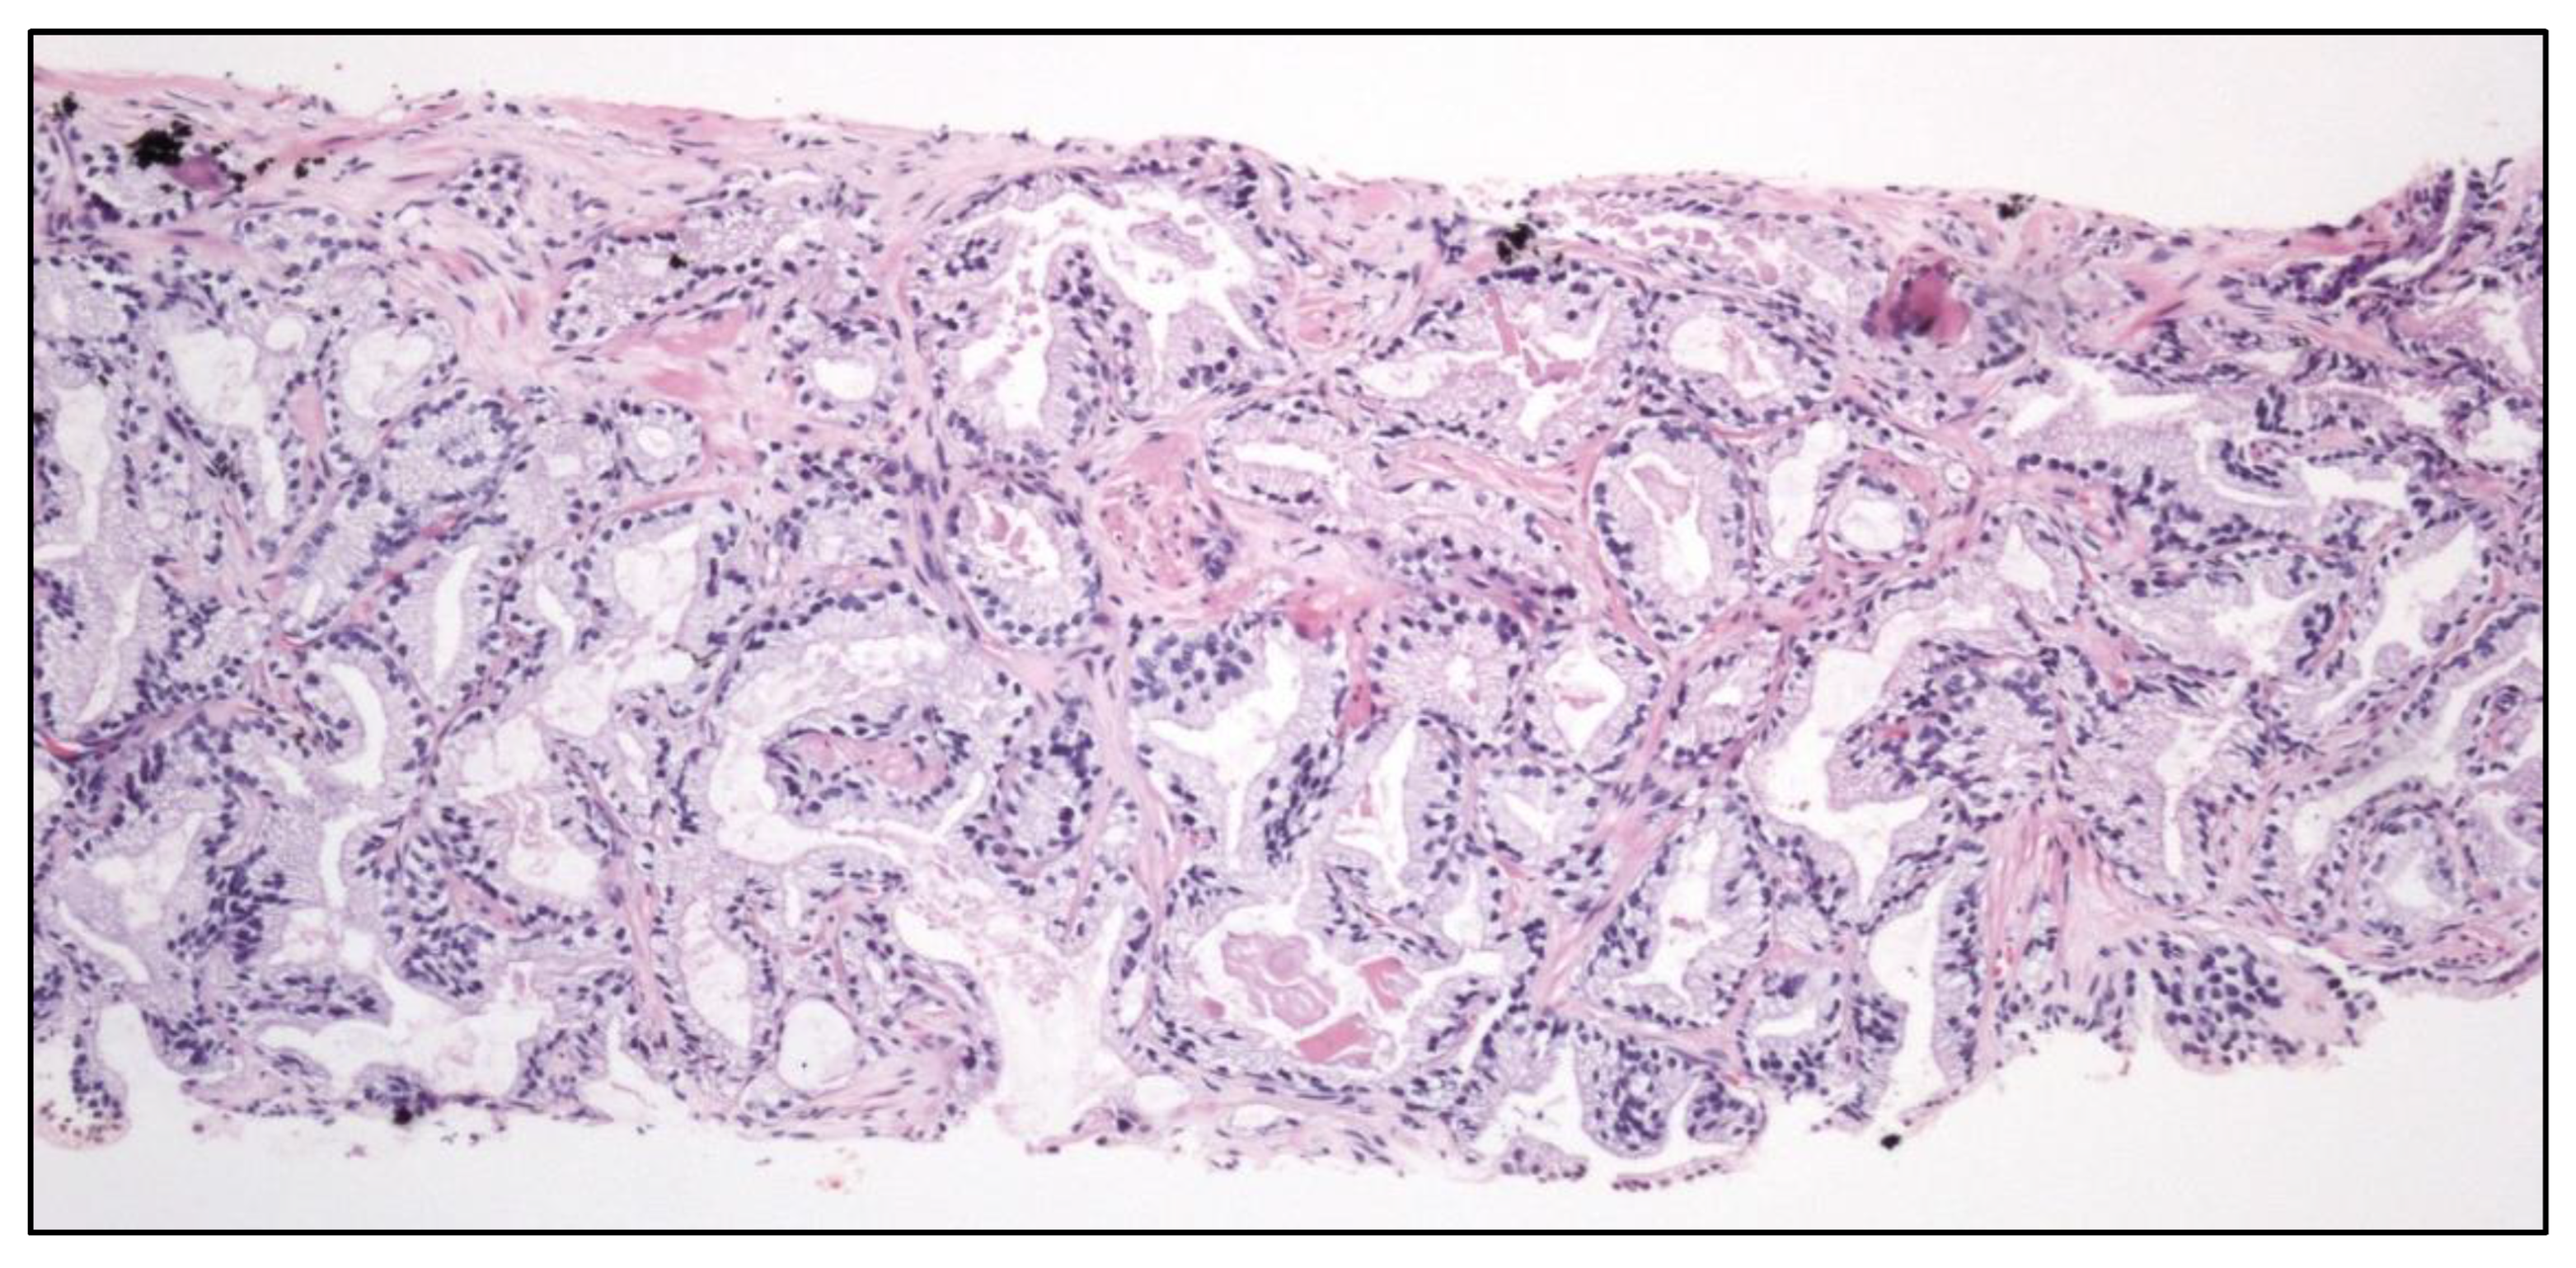

Within the group of germ cell tumors not related with in situ germ cell neoplasia, the term spermatocytic tumor (Figure 4) is maintained. To note, the name “carcinoid tumor” is no longer used. The testicular neuroendocrine tumor is recalled as “prepuberal testicular neuroendocrine tumor” since most of them arise in prepuberal teratomas. The sertoliform cystadenoma moves from the adnexal tumors group to the cluster of Sertoli cell tumors.

Well-differentiated papillary mesothelial tumor (Figure 4).

Figure 4. Typical histology of spermatocytic tumor (left) (original magnification, x250) and well differentiated papillary mesothelial tumor (right).